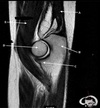

How well did you know this?

1

Not at all

2

3

4